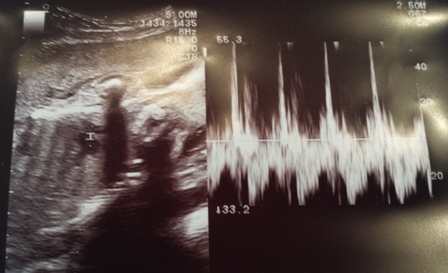

Een regelmatige onregelmatige hartslag? Die wil je NIET horen.

'Ik denk dat het beter is als toch een gynaecoloog even meekijkt.' Dat is een zin die je als aanstaande moeder niet wil horen uit de mond van je verloskundige. Maar ik hoorde 'm wel. En dat allemaal vanwege een regelmatige onregelmatige hartslag van 't kind in mijn buik. En mijn … [Read more...] about Een regelmatige onregelmatige hartslag? Die wil je NIET horen.